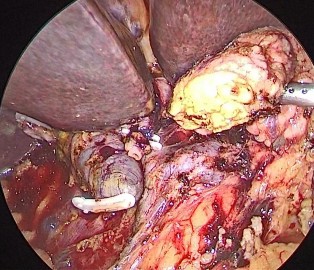

Bệnh nhân 3: Đỗ Văn M, 1952 (67 tuổi) Mã số bệnh án: 19-03-00991

Chẩn đoán: Tắc mật do u bóng Vater Phẫu thuật: PTNS hỗ trợ cắt khối tá tụy

| |

Ảnh 1. Mỏm tụy và ống mật chủ | Ảnh 6. Vết mổ sau 12 tháng |